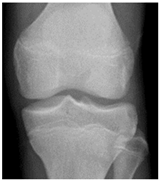

In the local dataset, we have selected 60 adult patient files of men and women with knee disorders who were radiographically examined at the Radiology Department of the El Kelaa des Sraghna Provincial Hospital. Each file consists of one or more knee radiographs in Dicom format as presented in Figure 7. The images were acquired using a standard ITALRAY radiology table. After analysis, 30 images with implants and non-posterior-anterior examination views were excluded and 30 left and right Dicom knees were retained to validate this work. To make the validation local dataset, the ROI was selected manually as illustrated in Figure 8. Then, each patient’s file was presented to a rheumatologist with PNG images. In case of disagreement between our diagnostic system and the rheumatologist, a radiologist was consulted for arbitration to make the final decision.

Figure 8.

Manual ROI selection. (a) ROI selection of a man’s knee. (b) ROI selection of a woman’s knee.